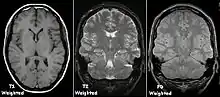

Examples of T1-weighted, T2-weighted and PD-weighted MRI scans

Each tissue returns to its equilibrium state after excitation by the independent relaxation processes of T1 (spin-lattice; that is, magnetization in the same direction as the static magnetic field) and T2 (spin-spin; transverse to the static magnetic field). To create a T1-weighted image, magnetization is allowed to recover before measuring the MR signal by changing the repetition time (TR). This image weighting is useful for assessing the cerebral cortex, identifying fatty tissue, characterizing focal liver lesions, and in general, obtaining morphological information, as well as for post-contrast imaging. To create a T2-weighted image, magnetization is allowed to decay before measuring the MR signal by changing the echo time (TE). This image weighting is useful for detecting edema and inflammation, revealing white matter lesions, and assessing zonal anatomy in the prostate and uterus.